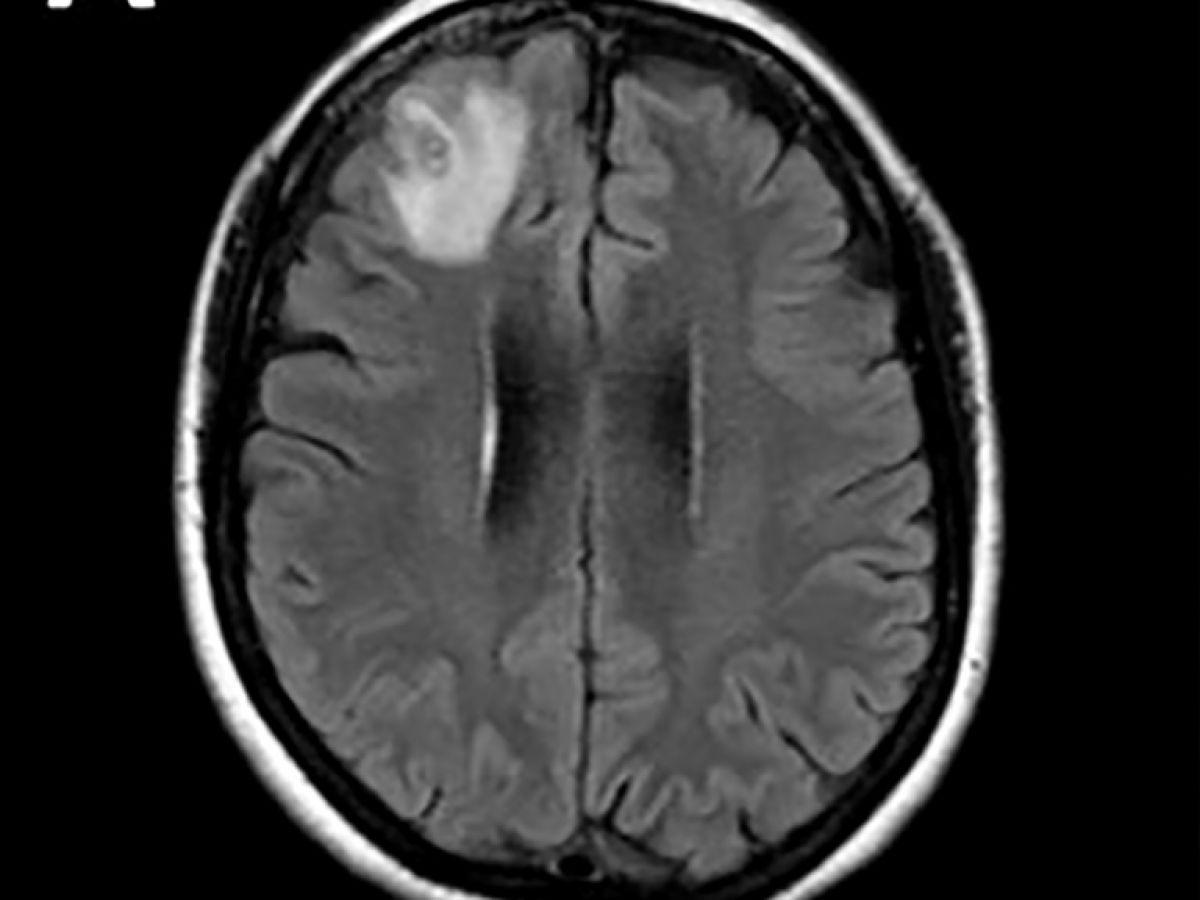

Africa-Press – São Tomé e Príncipe. Un ver rond, qui parasite généralement les serpents, a été découvert pour la première fois sur un être humain. Il a été extrait “vivant et se tortillant” du cerveau d’une Australienne lors d’une intervention chirurgicale, ont annoncé mardi des médecins australiens. Les médecins ont découvert une “lésion atypique”, grâce à un examen IRM, dans la partie frontale du cerveau de cette femme âgée de 64 ans qui souffrait de pertes de mémoire.

“À notre connaissance, c’est également le premier cas impliquant le cerveau d’une espèce de mammifère, humaine ou autre”, a-t-il précisé. Cette découverte a fait l’objet d’un article dans la revue “Emerging Infectious Diseases”. Les scientifiques pensent que l’Australienne a été parasitée par des plantes comestibles, probablement contaminées par des larves présentes dans des excréments de serpents. Le parasite, dont la “structure en forme de fil” est apparue sur les scanners cérébraux, a ensuite été identifié grâce à des tests ADN. “Il n’est jamais facile ni souhaitable d’être le premier à être malade de quoi que ce soit au monde”, a ajouté le Dr Senanayake, “je ne saurais trop exprimer notre admiration pour cette femme, qui a fait preuve de patience et de courage tout au long de ce processus.” Selon le Dr Senanayake, il est “probable que d’autres cas soient identifiés à l’avenir”.